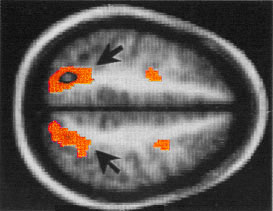

Нейрофизиологи из Принстонского и Пенсильванского университетов выполнили исследование, в котором испытуемым предлагалось сначала запомнить множество изображений, а потом назвать их в произвольном порядке. На протяжении всего эксперимента активность мозга фиксировалась при помощи магнитно-резонансного томографа (fMRI).

В ходе эксперимента обнаружилось, что эти три категории объектов запоминаются в разных участках мозга: картина активности мозга менялась в зависимости от того, к какой категории относился запоминаемый объект. Когда испытуемые вспоминали объекты, исследователи наблюдали картину возбуждения мозга, аналогичную той, которая была в момент запоминания. Когда человек переключался с объектов одной категории на другую, то регистрировалось и соответствующее изменение активности мозга. При этом исследователи могли определить категорию очередного объекта, за несколько секунд до того, как испытуемый его называл.